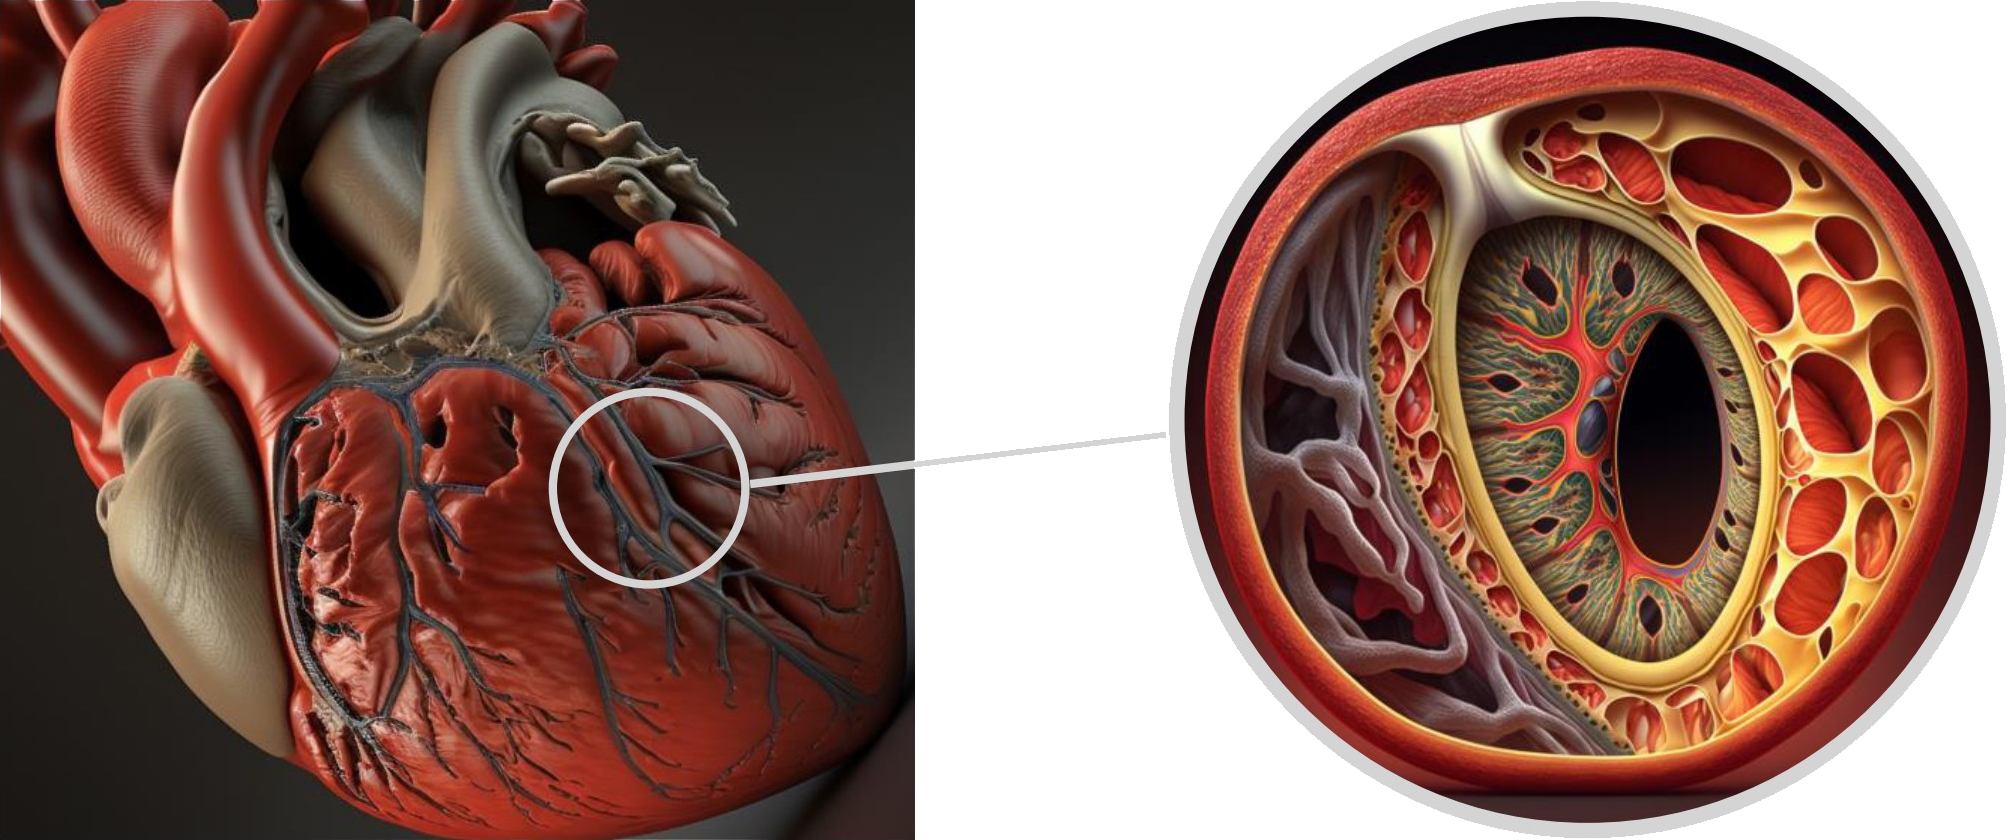

The arterial wall is composed of three distinct layers. The innermost layer, known as the tunica intima, consists mainly of endothelial cells and connective tissue. The middle layer, called the tunica media, is comprised of smooth muscle cells, while the outer layer, the tunica adventitia, is made up of collagen and elastic fibers and includes the vasa vasorum [5]. Coronary dissection occurs when an intramural hematoma forms, leading to the separation of the tunica intima from the outer layers and creating a false lumen that protrudes into the real lumen, ultimately reducing blood flow (Fig. 9).

Fig. 9.

Fig. 9.Tridimensional representation of LAD coronary artery dissection. LAD, left anterior descending.